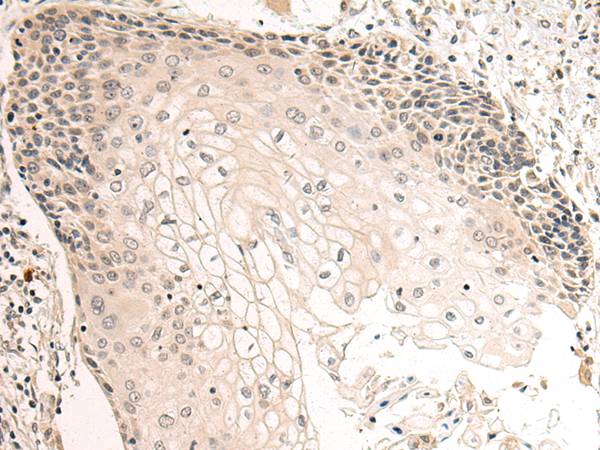

分类: 科研抗体货号: P05885别名: CT119; VSIG3; Igsf13; BT-IgSF; CXADRL1应用: IHC反应种属: Human